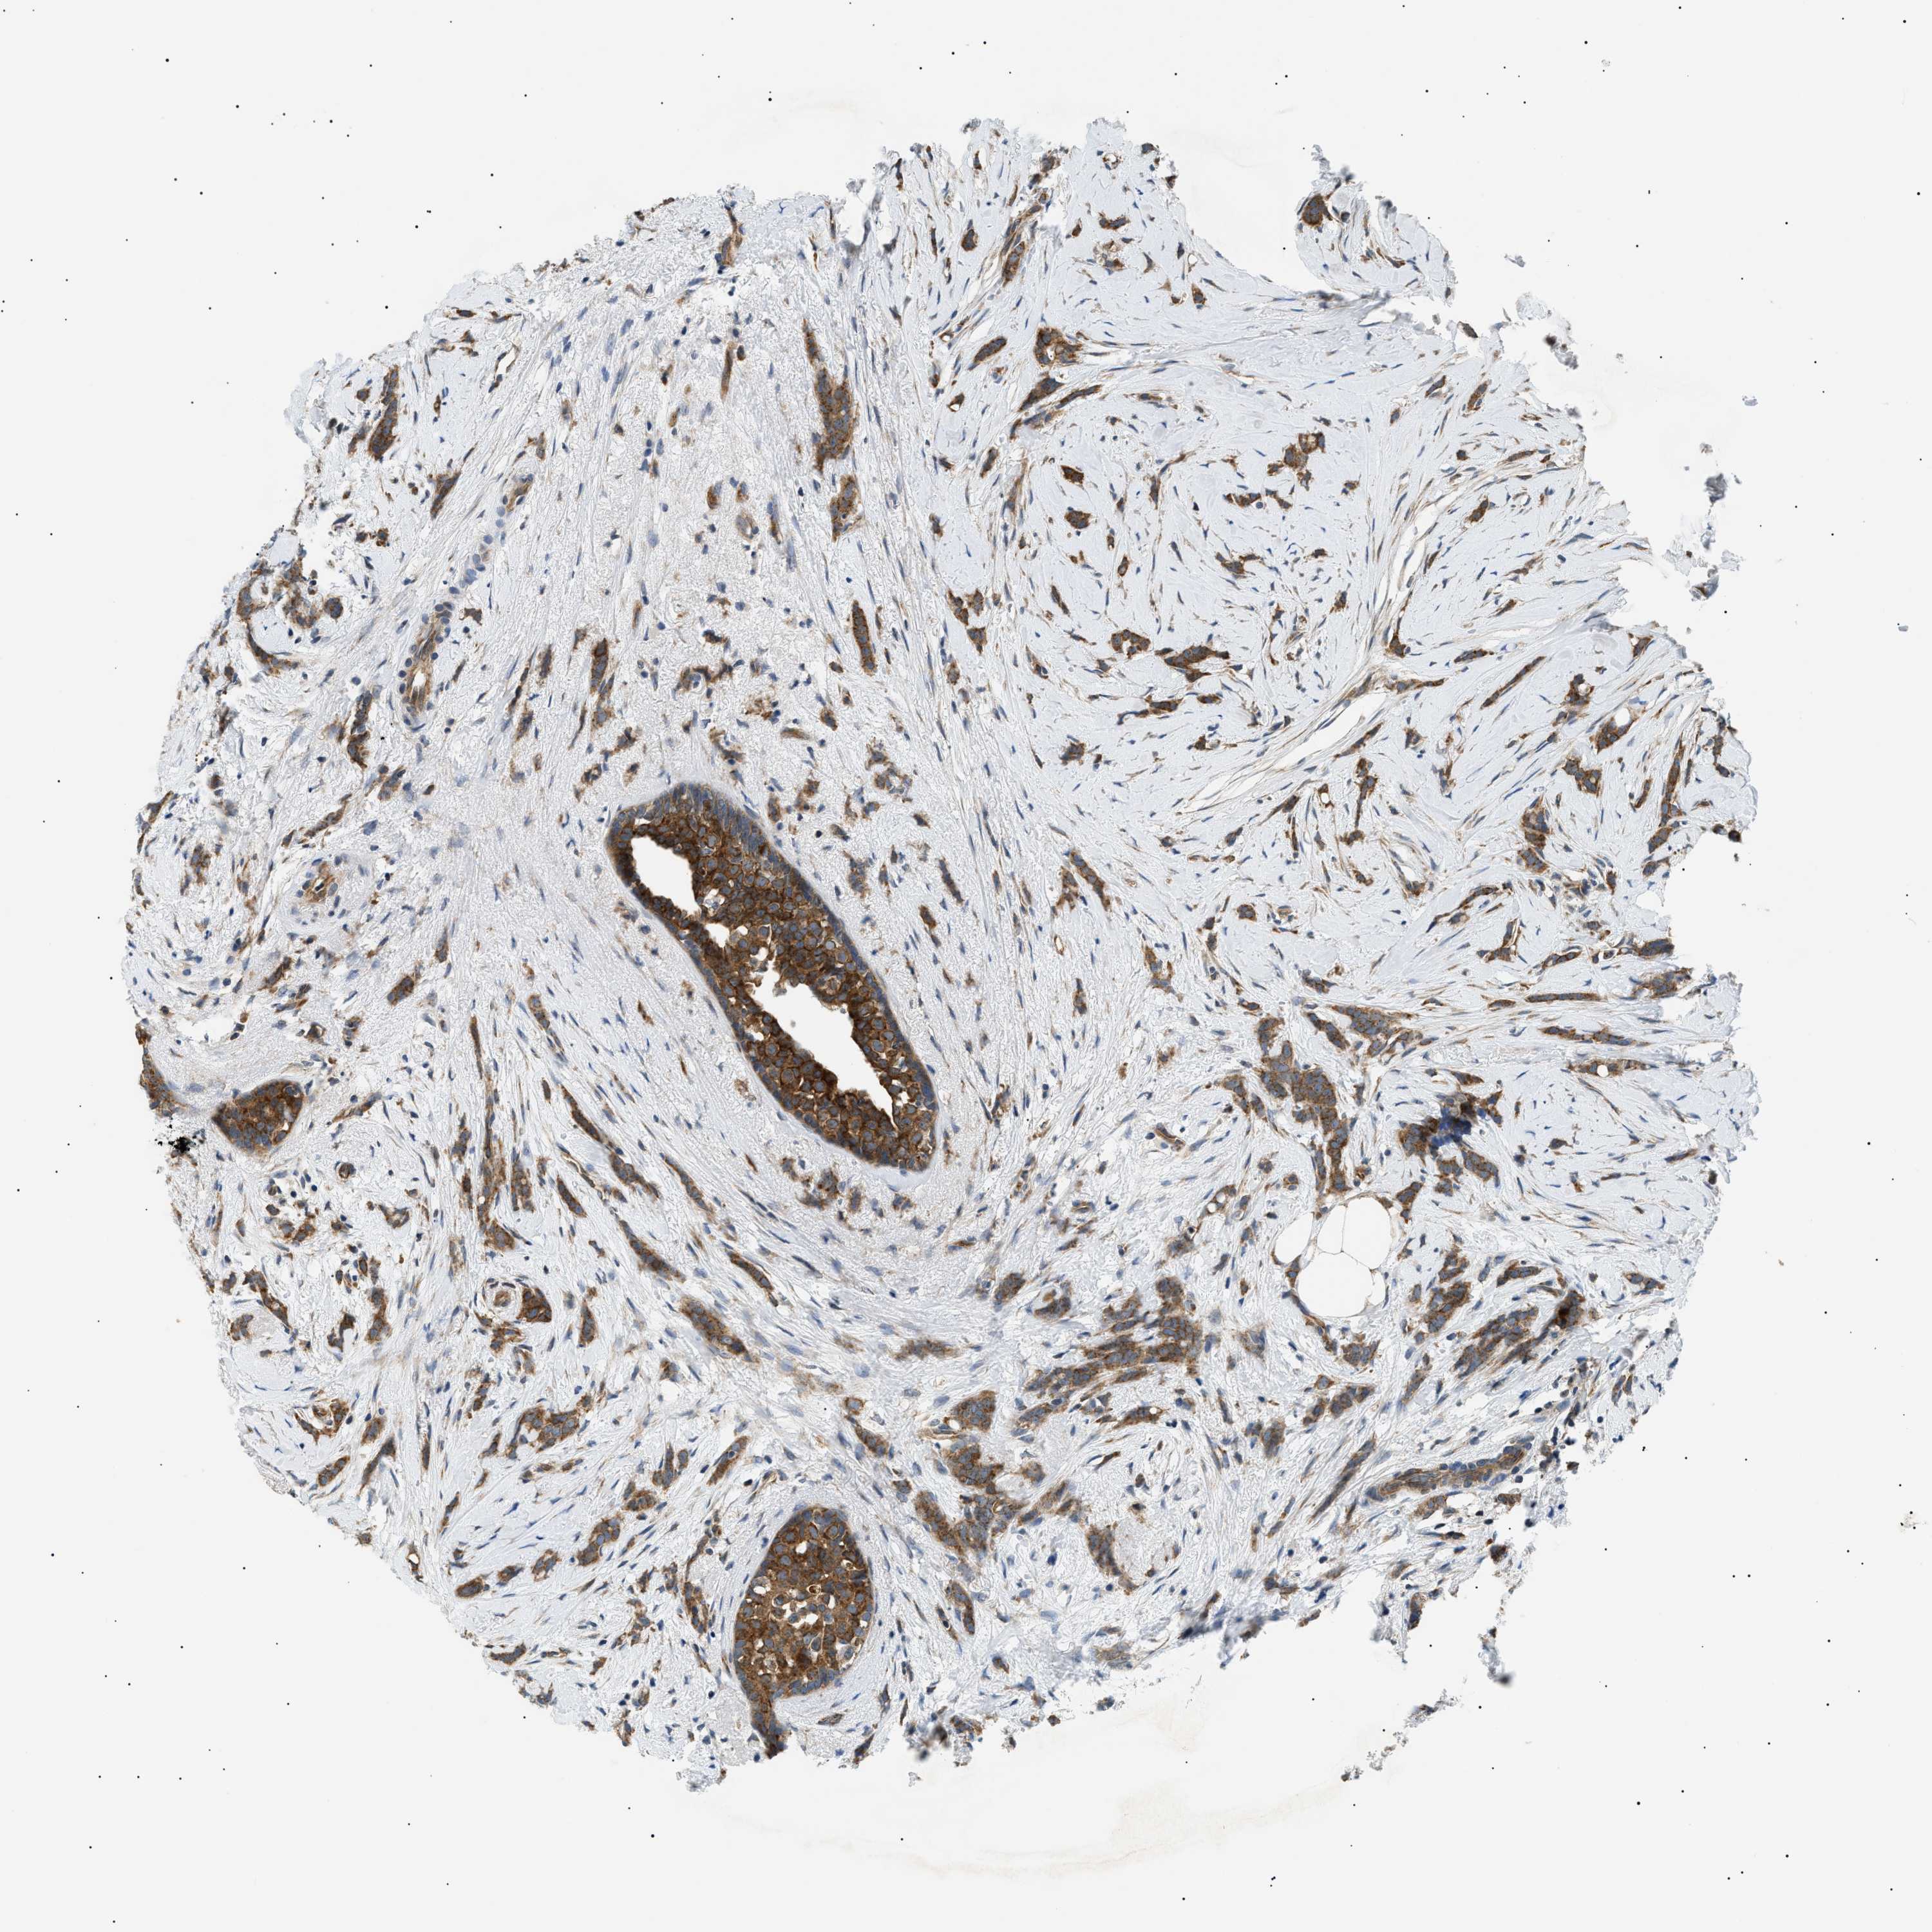

CANCER BREAST CANCER Show tissue menu

BRCA TCGA BRCA VALIDATION PROTEIN EXPRESSION